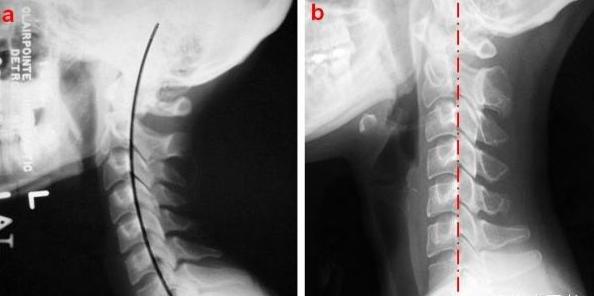

2.关节功能紊乱型:

病因主要是椎小关节错位、椎小关节滑膜嵌顿。

从X光可看到脊椎连线异常:生理曲度改变,椎体滑脱等、脊柱侧弯、棘突偏歪等。以上描述与临床症状的定位诊断不一致。

骨关节触诊可以发现偏歪、不对称、隆起。

治疗上根据不同的错位形式,选用不同的正骨手法效果明显。